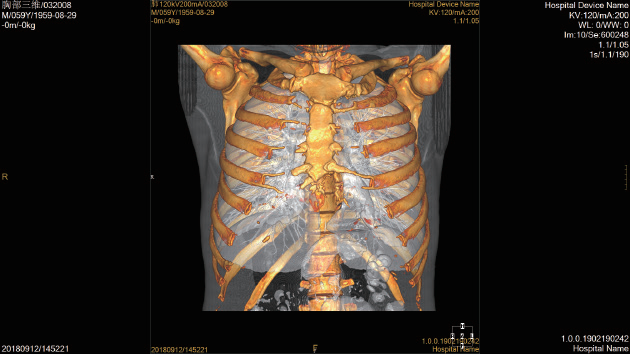

Умное рабочее место медицинского отображения

Согласно международному стандарту DICOM 3,0, само-разработанное рабочее место CIW совершенно исполняет с

стандарты медицинских изображений, включая функции получать, обрабатывающ, анализирующ, управляющ, помещающ в архив

запрашивающ, просматривающ, печатающ стандартный выход формата изображения, сочинительство отчета и так далее. В то же время, CIW также

содержит много других предварительных клинических применений.